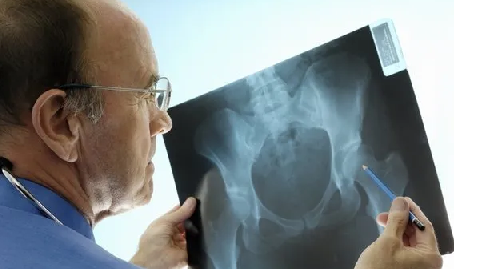

Kemik erimesi, ilerleyen yaşlarda ortaya çıkan ve özellikle menopoz sonrası kadınları sıklıkla etkileyen önemli sorunlardan biri. Bu riskleri ortadan kaldırmak için ise dikkat edilmesi gereken bazı durumlar bulunuyor. Romatolog Dr. Taher Mahmud, osteoporozun yıkıcı etkileri olabildiğini, ancak bu durumun tedavi edilebilir ve önlenebilir olduğunu söyledi. İşte kemik erimesi riskini bitirecek o adımlar…